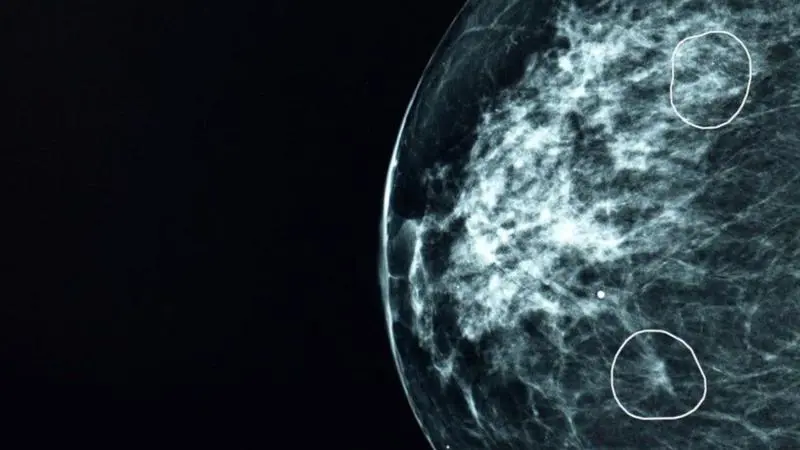

برۆکلی سولفۆرافان لەخۆدەگرێت. سولفۆرفان پێکهاتەیەکی ڕووەکییە کە لە سەوزەی کەلەم دا هەیە و دەتوانێت تایبەتمەندی دژە شێرپەنجەی هەبێت، توێژینەوەکان دەریان خستووە کە سولفۆرافان قەبارە و ژمارەی خانەکانی شێرپەنجەی مەمک بە ڕێژەی ٧٥٪ کەم دەکاتەوە.

هەروەها توێژینەوەیەکی لەسەر ئاژەڵان دەرکەوتووە کە چارەسەرکردنی مشک بە دەرمانی سولفۆڕفان یارمەتیدەرە بۆ لەناوبردنی خانەکانی شێرپەنجەی پرۆستات و قەبارەی وەرەمەکە بە ڕێژەی زیاتر لە 50% کەم دەکاتەوە، بەپێی ئەو دۆزینەوانە خواردنی سەوزەی خاچدارتر وەک برۆکلی کاریگەری لەسەر مەترسی تووشبوون بە شێرپەنجەی کۆڵۆن و ڕیخۆڵە دەبێت.

پێداچوونەوەیەک بۆ 35 توێژینەوە دەرکەوتووە کە خواردنی زیاتری سەوزەی کەلەم پەیوەندی بە کەمبوونەوەی مەترسی تووشبوون بە شێرپەنجەی قۆڵۆن و کۆڵۆن و ڕیخۆڵە هەیە، لە هەفتەیەکدا چەند ژەمێک برۆکلی لەگەڵ ژەمەکانت بخۆ.